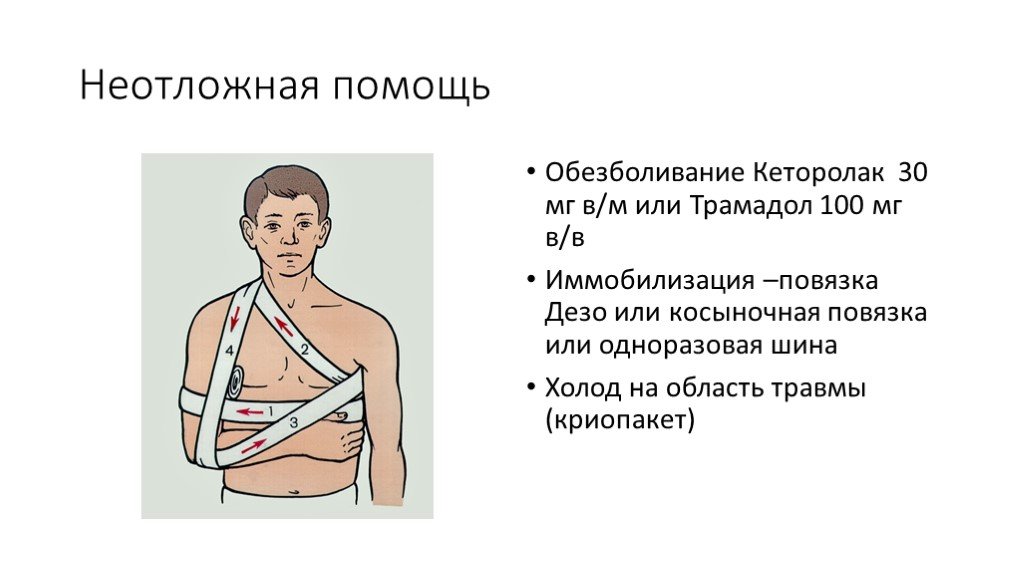

Вывихи и переломы ключицы презентация - 85 фото